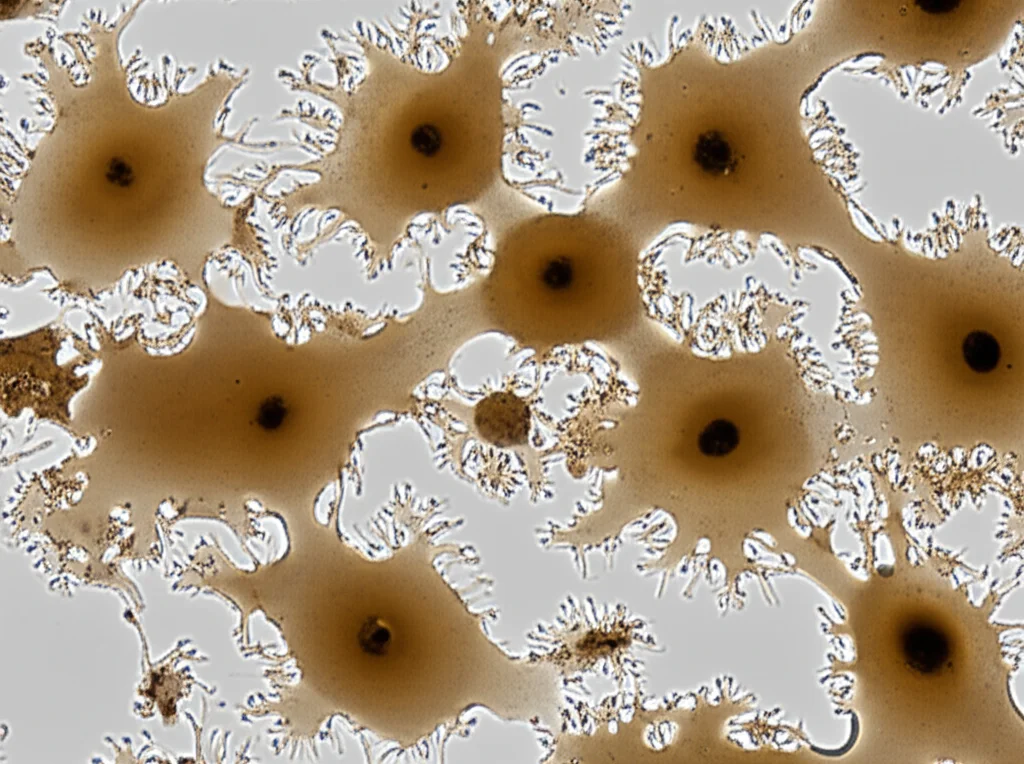

Ma non ci siamo fermati qui. Volevamo capire se fossero proprio le OMV di P. gingivalis a fare il “lavoro sporco”. Così, abbiamo isolato queste vescicole e le abbiamo messe a contatto con due linee cellulari di carcinoma orale umano, chiamate CAL27 e HN6. Per essere sicuri dei risultati, abbiamo usato diverse concentrazioni di OMV e gruppi di controllo.

I risultati sono stati piuttosto chiari:

- Proliferazione cellulare: Le OMV di P. gingivalis hanno promosso la crescita (proliferazione) sia delle cellule CAL27 che delle HN6. L’effetto era più marcato con una concentrazione maggiore di OMV (50 µg/mL). Immaginate le cellule tumorali che iniziano a moltiplicarsi più velocemente sotto l’influenza di queste vescicole. Abbiamo confermato questo dato con due test diversi, il CCK-8 e l’EdU assay, che misurano proprio la capacità delle cellule di dividersi.

- Migrazione cellulare: Qui la storia si è fatta un po’ più specifica. Le OMV hanno aumentato significativamente la capacità di migrazione delle cellule HN6, sia in orizzontale (come se dovessero “guarire una ferita” in una piastra di coltura) sia in verticale (attraversando una membrana in un test chiamato Transwell). Anche in questo caso, l’effetto era dose-dipendente. Curiosamente, sulle cellule CAL27, le OMV non hanno avuto un impatto significativo sulla migrazione. Questo ci suggerisce che l’effetto potrebbe dipendere dal tipo specifico di cellula tumorale.

Quindi, queste piccole vescicole sembrano davvero in grado di dare una “spinta” al tumore, facendolo crescere di più e, almeno in alcuni casi, rendendolo più incline a diffondersi.